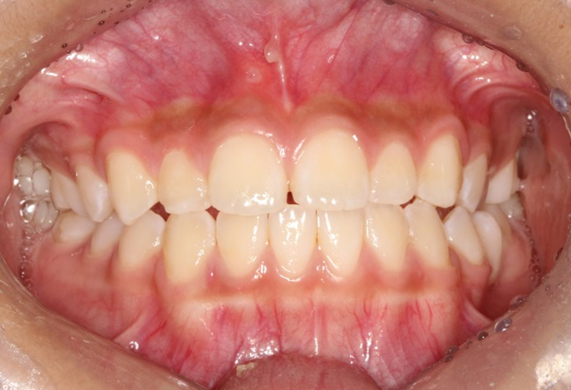

부분교정

발치 없이 기존의 어금니 교합은 유지하면서 교정이 필요한 앞니만 장치를 부착하여 교정하는 방식입니다. 짧은 기간안에 원하는 결과를 얻을 수 있어 만족도가 높은 치료입니다.

부분교정 CASE